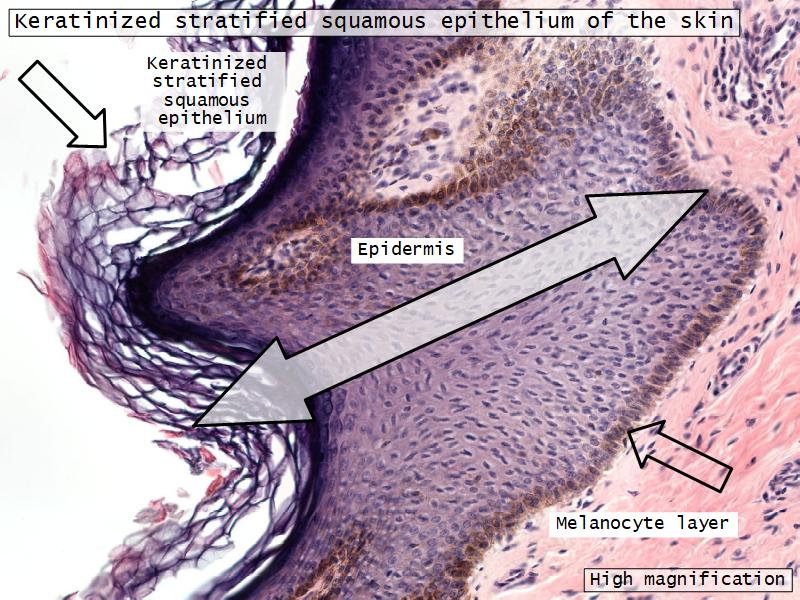

What are the main morphological features of the nipple?

Morphology

- Covered with skin

Skin

- Keratinized stratified squamous epithelium